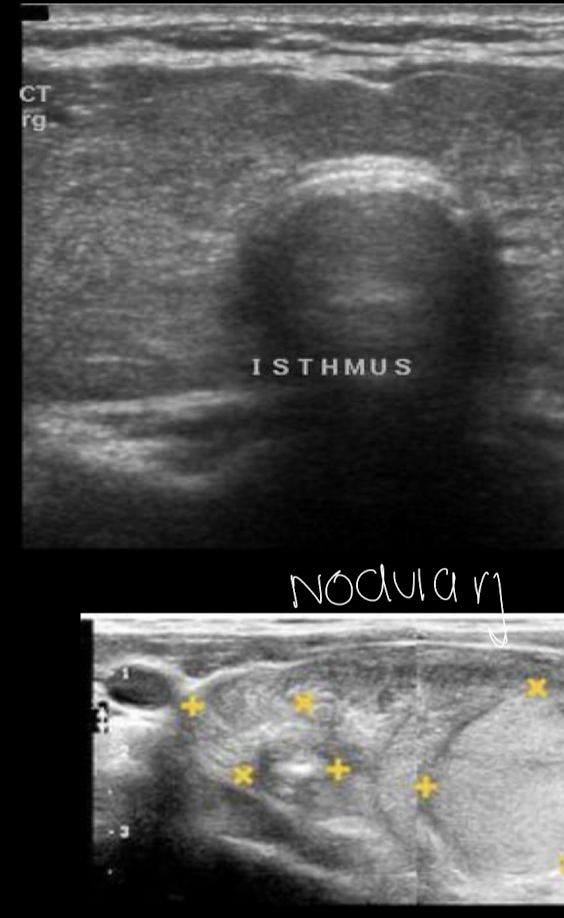

Bocio imagen

USG

valorar tamaño de tiroides, lesiones, vascularización

Tipos de bocio

Difuso o nodular